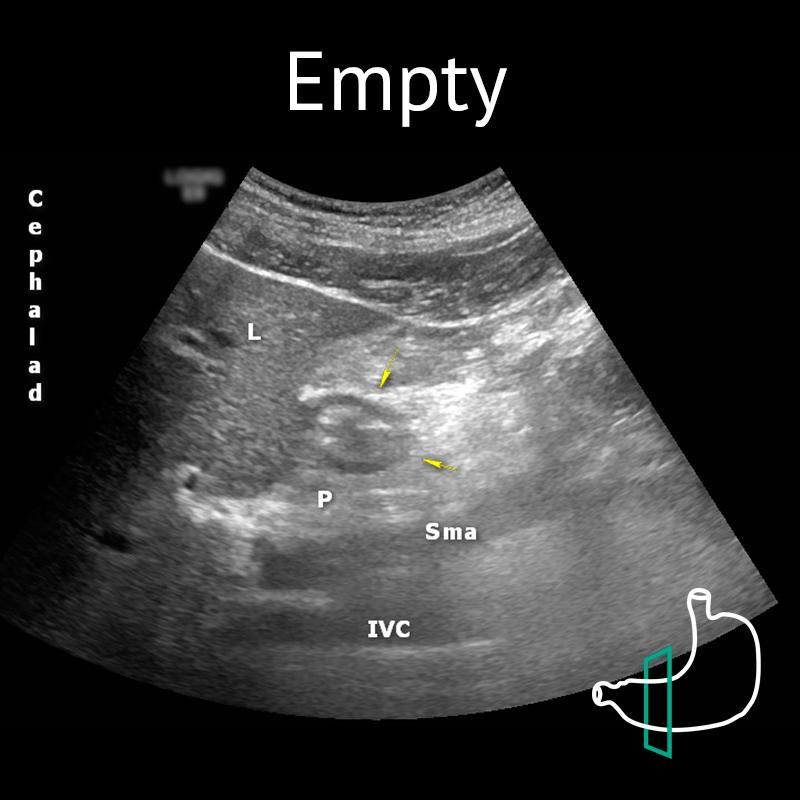

IVC: inferior vena cava; L: liver; P: pancreas; Sma: superior mesenteric artery; Yellow arrows: antrum